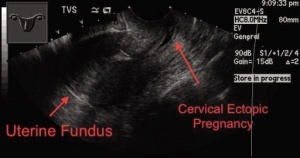

Ectopic pregnancy

- Implantation of blastocyst outside of endometrium

- Occur in fallopian tubes, cervix, ovaries, peritoneal cavity, or scar of prior uterine surgery

- Most definitive sonographic sign is gestational sac with yolk sac, embryo, or fetal heart beat outside of the endometrium

- Cervical Pregnancy

- Implantation of gestational sac below internal cervical os

- Can cause life-threatening hemorrhage

- Must distinguish between cervical ectopic and spontaneous abortion at level of cervix: